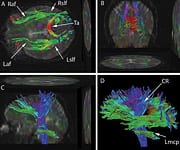

Traumatic brain injury (TBI) is often referred to as the "signature wound" of both the Iraq and Afghanistan wars. Traumatic brain injury occurs when a sudden trauma to the head disrupts brain function. In both these wars, however, even close proximity to the force of an explosion can be just as devastating. Most of the reported traumatic brain injury among Operation Enduring Freedom and Operation Iraqi Freedom veterans has been traced to improvised explosive devices, or IEDs. "Traumatic brain injury can be caused by a direct impact, or by acceleration alone," explains Dr. Mark L. Gordon, interventional endocrinologist and traumatic brain injury treatment specialist at Millennium Health Centers in Los Angeles. "Brain trauma also causes secondary injury, which takes place in the minutes and days following the injury," he adds. "These processes include alterations in cerebral blood flow and increased pressure within the skull, contributing substantially to damage from the initial injury." Gordon says traumatic brain injury can cause a host of physical, cognitive, emotional, and behavioral effects, some of which can be difficult to detect. Symptoms can appear immediately or weeks to years following the injury. "Insidious traumatic brain injury can be difficult to detect," Gordon says. "Localized damage to the frontal and occipital lobes occurs when the brain collides with the skull. Increasingly, we are discovering that traumatic brain injury is also a causative factor for accelerated hormonal deficiencies." These deficiencies, says Gordon, can cause a host of psychological, physiological, and physical manifestations, including depression, outbursts of anger, anxiety, mood swings, memory loss, inability to concentrate, learning disabilities, sleep deprivation, increased risk for heart attacks, strokes, high blood pressure, diabetes, loss of libido, menstrual irregularities, premature menopause, obesity, loss of lean body mass, muscular weakness, and a number of other medically documented conditions. What's more, Gordon points out that veterans suffering from these forms of psychological damage due to traumatic brain injury are frequently misdiagnosed and have their injury erroneously downgraded to post-traumatic stress disorder (PTSD). Moreover, especially in mild traumatic brain injury cases, symptoms at the initial time of injury may go unrecognized or unnoticed, but patients will still develop hormone deficiencies. Unfortunately, the government is slow to accept the link between traumatic brain injury and hormonal deficiencies. Dr. Gordon's Epiphany

By sheer serendipity, many years ago Dr. Gordon provided care for a young man with a history of numerous sports-related head injuries, whose parents were themselves patients at the clinic. The young man's symptoms long outlasted the immediate effects of his acute injury and included loss of concentration, memory, mental energy, focus, and physical well-being, often accompanied by loss of lean muscle mass and an increase in body fat. The parents, familiar with the effects of hormonal imbalances, naturally assumed that their son's problems might reflect an endocrine problem of his own. And indeed, many of his symptoms resembled those of adult patients with so-called hypopituitarism, or loss of pituitary gland function. The pituitary gland is located at the base of the brain and is sometimes called the "master" gland of the endocrine system, because it controls the functions of the other hormone- secreting glands. Gordon, who is nothing if not intellectually curious, hit the books. What he found was startling and life-changing, for himself as a clinician, for his young patient, and now for scores of additional victims of traumatic brain injury. Symptoms of Traumatic Brain Injury Mimic Pituitary DysfunctionDr. Gordon found a wealth of published literature suggesting that traumatic brain injury causes pituitary dysfunction, confirming his initial hunch.1 Although the figures vary between studies, at least 50% (and up to 76%) of traumatic brain injury victims show some loss of pituitary hormone function immediately after the brain injury.2-4 In general, the more severe the original brain injury, the more profound the hormonal deficits, although hormone deficiency or insufficiency (levels in the low "normal" range) are seen even in patients with mild traumatic brain injury.5-9 And while about 58% of patients recover their normal pituitary function within one year of their head injury, a shocking 52% develop new pituitary hormone deficiencies after one year. 10,11 Those deficits include reductions in many different pituitary hormones, including those that regulate the thyroid gland, the adrenal glands (that produce cortisol, DHEA, and other vital hormones), the gonads (where estrogen and testosterone are produced), and growth hormone.3,4,12,13 The severity of the hormone deficiencies correlates strongly with the kinds of symptoms Dr. Gordon was seeing in his patient. For example, patients with growth hormone deficiency or insufficiency had significantly worse disability rating scores, greater rates of depression, worse quality of life, lower energy, greater fatigue, and poorer emotional well-being, compared to brain injury patients with normal hormonal levels.14,15 Dr. Gordon's hunch was borne out: patients with traumatic brain injury often have pituitary hormone deficiencies or insufficiencies, especially in growth hormone. And those defects are closely associated with the persistent neurological, psychological, and emotional deficits that are so tragically common in survivors of traumatic brain injury. And where are you most likely to find a high concentration of survivors of traumatic brain injury? The United States military.